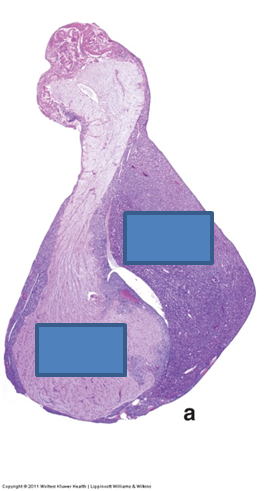

Identify the indicated structures.

AP: anterior pituitary

PP: posterior pituitary

P: pituitary stalk (infundibulum)

H: hypothalamus

V: ventricle

O: optic chiasm